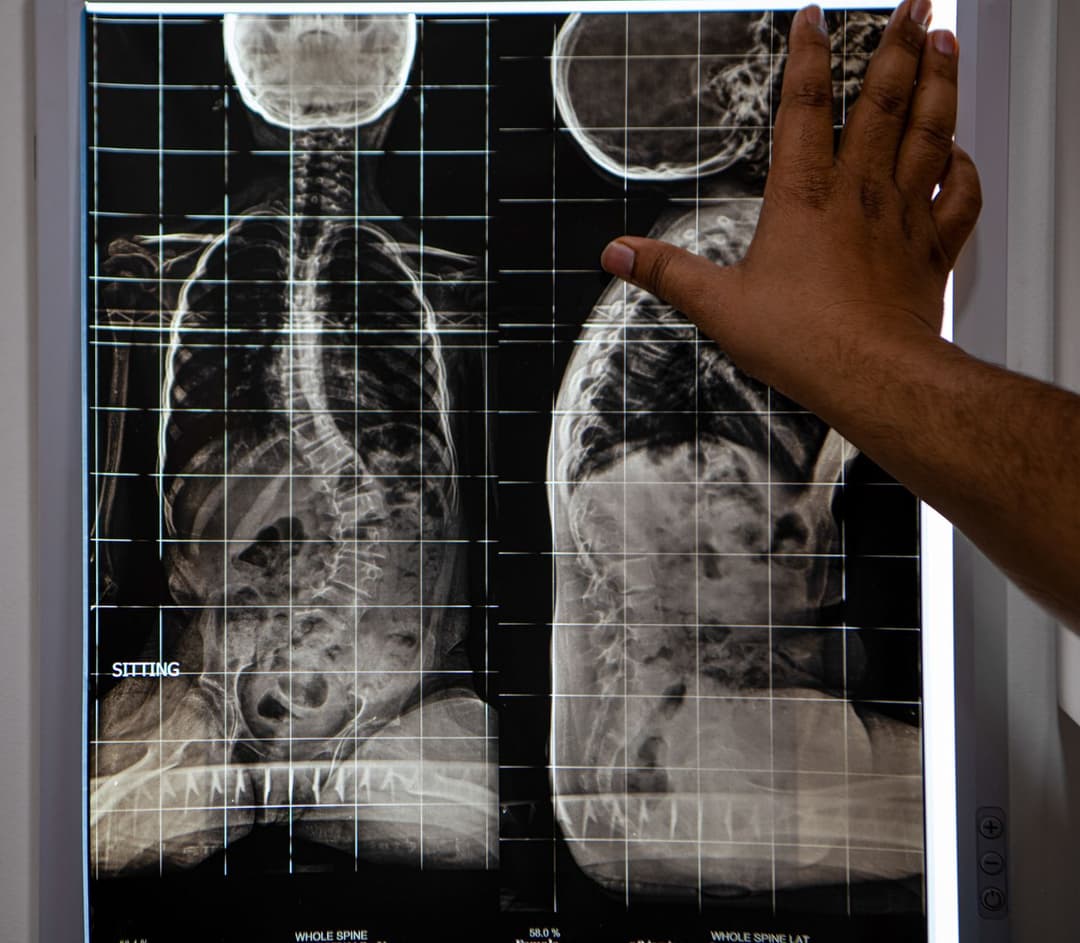

Roshan’s scoliosis was diagnosed when he was 21, and he was told he would never dance. Scoliosis causes the spine to curve sideways. Everybody has regular curves in their spines, but in kids and teenagers with it, the spine – or parts of it – curve abnormally in the shape of an ‘S’ or ‘C’.

The teenage Sebanti travelled from her home in South 24 Parganas to Kolkata to have surgery for adolescent idiopathic scoliosis (AIS). The procedure involved the insertion of two rods and 14 screws in her back to straighten her spine.